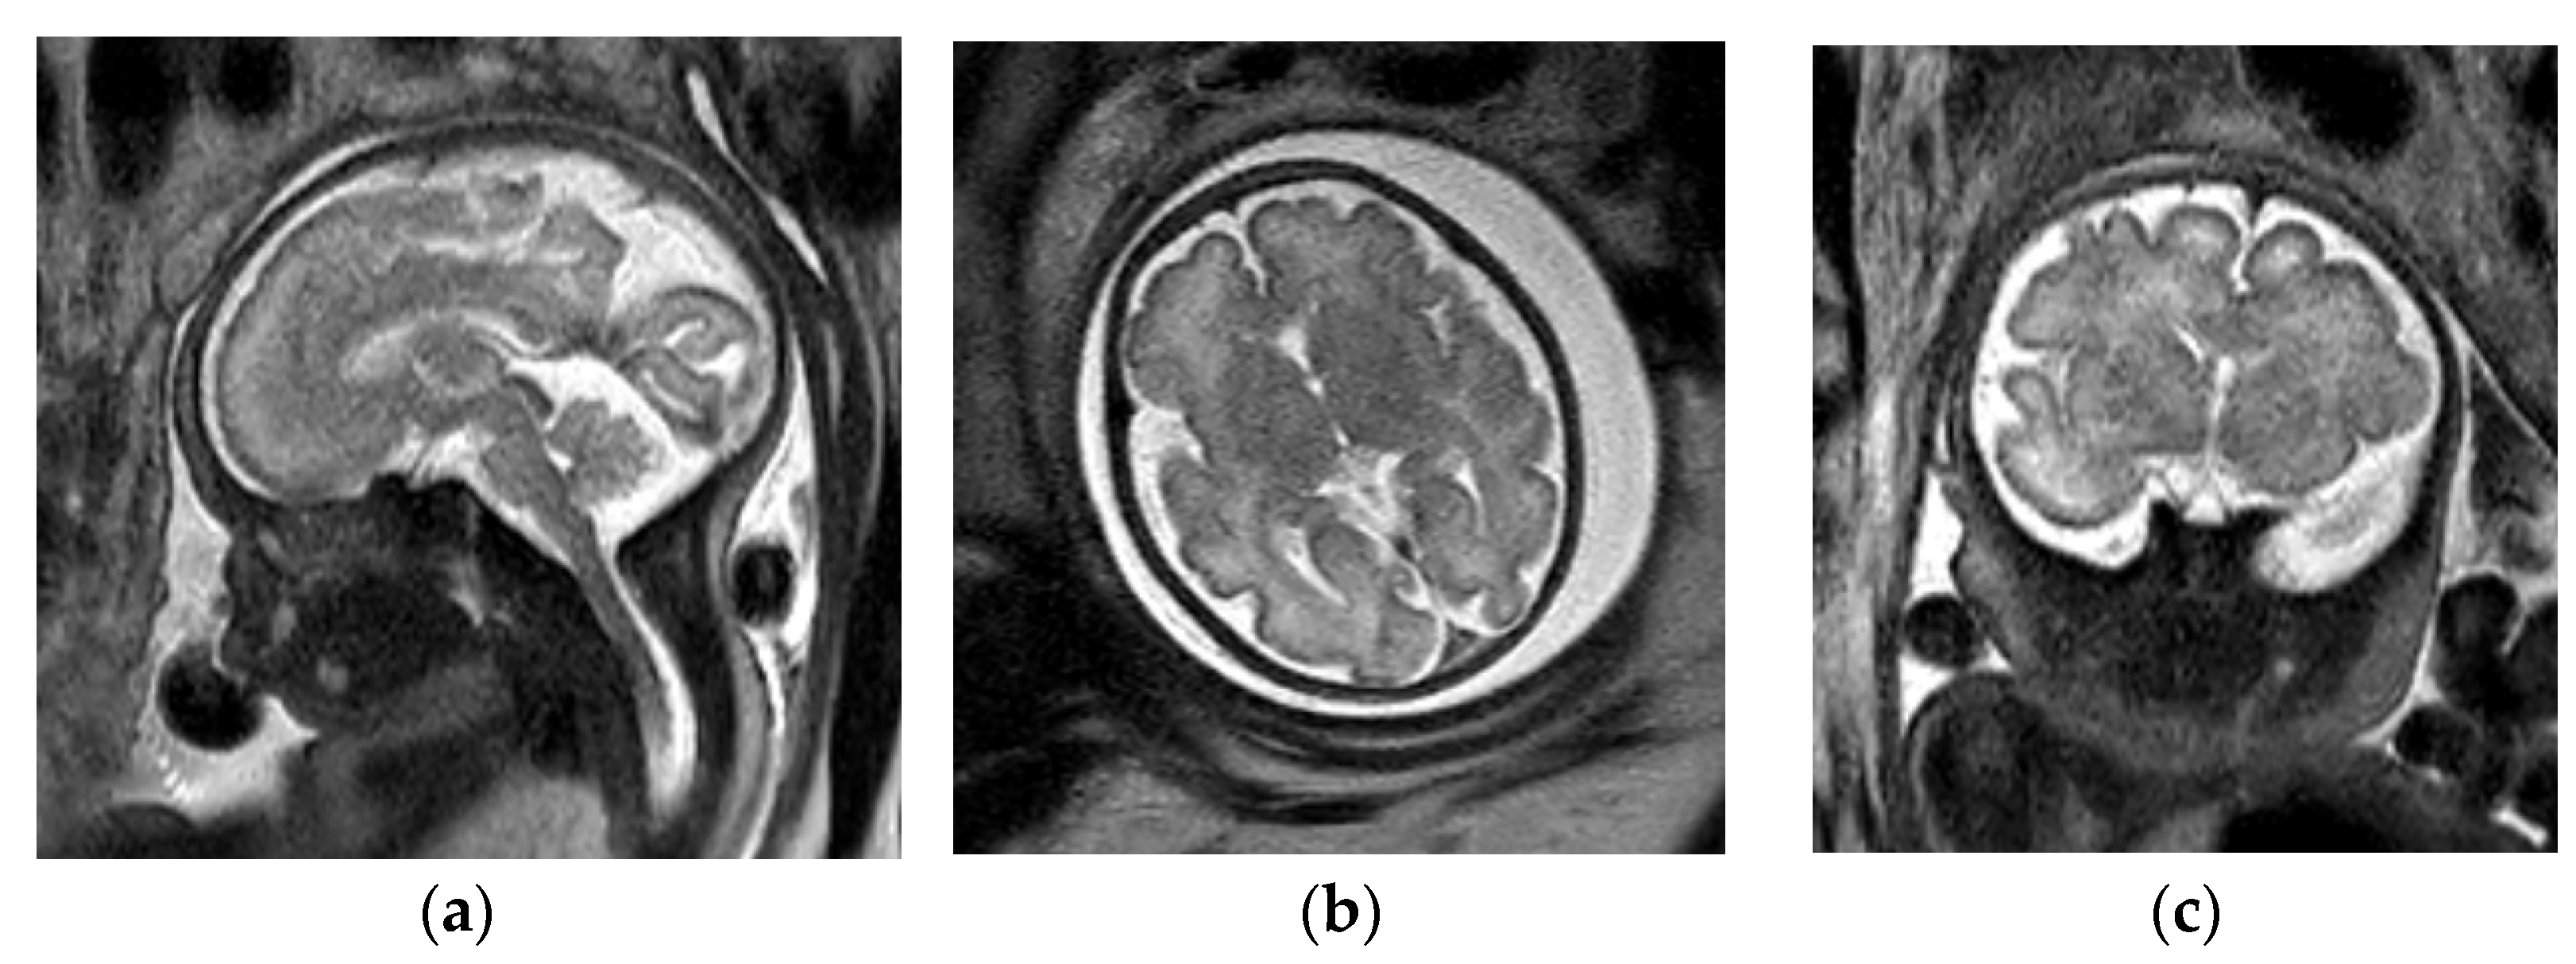

3.1.2. Chiari II Malformation

- Stevenson, K.L. Chiari Type II malformation: Past, present, and future. Neurosurg. Focus 2004, 16, 1–7. [Google Scholar] [CrossRef]

- Van den Hof, M.C.; Nicolaides, K.H.; Campbell, J.; Campbell, S. Evaluation of the lemon and banana signs in one hundred thirty fetuses with open spina bifida. Am. J. Obstet. Gynecol. 1990, 162, 322–327. [Google Scholar] [CrossRef]

- Sutton, L.N.; Adzick, N.S.; Bilaniuk, L.T.; Johnson, M.P.; Crombleholme, T.M.; Flake, A.W. Improvement in hindbrain herniation demonstrated by serial fetal magnetic resonance imaging following fetal surgery for myelomeningocele. J. Am. Med. Assoc. 1999, 282, 1826–1831. [Google Scholar] [CrossRef] [Green Version]

- Nagaraj, U.D.; Bierbrauer, K.S.; Zhang, B.; Peiro, J.L.; Kline-Fath, B.M. Hindbrain Herniation in Chiari II Malformation on Fetal and Postnatal MRI. AJNR Am. J. Neuroradiol. 2017, 38, 1031–1036. [Google Scholar] [CrossRef] [PubMed] [Green Version]